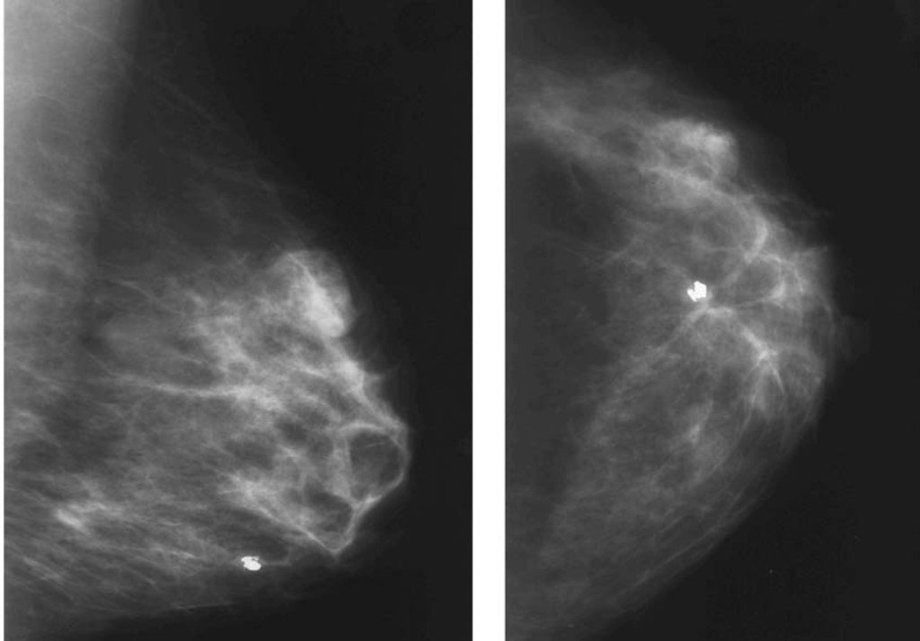

- ультразвуковые исследования груди;

Дифференциальная диагностика может потребовать проведения маммографии, компьютерной томографии железистых тканей, биопсии с последующим гистологическим анализом биоптата.